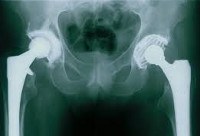

Первичное тотальное эндопротезирование тазобедренного сустава

Тотальный протез тазобедренного сустава. Оперативное вмешательство, при котором производится замена двух суставных поверхностей, образующих тазобедренный сустав (головка бедра и вертлужная впадина). Общие показания к протезированию - переломы вертлужной впадины со смещением, переломы головы и шеи бедренной кости с недостаточным кровоснабжением суставных поверхностей, патологические переломы, тяжелый остеоартрит бедра, артрит, некротические изменения в суставные поверхности. В зависимости от возраста и двигательной активности пациента возможна фиксация стента цементом и цементом.

После тотального эндопротезирования тазобедренного сустава.